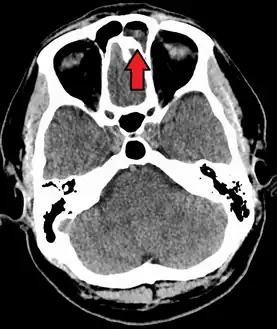

MRI image showing sinusitis. Edema and mucosal thickening appears in both maxillary sinuses.